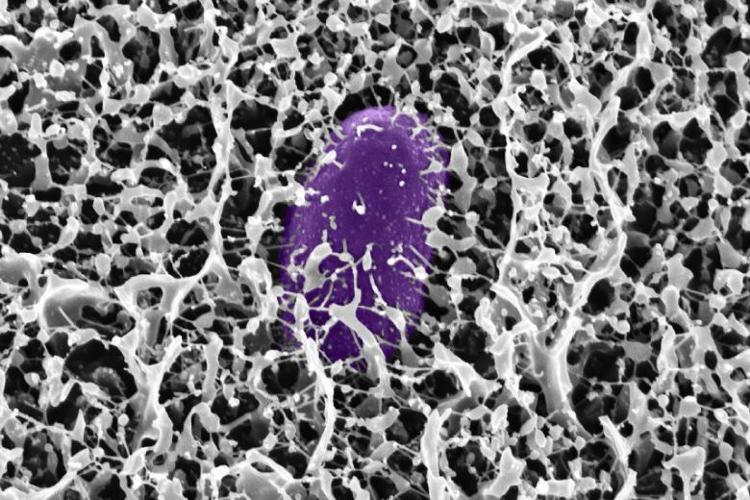

Il muco, spesso ridotto a semplice sostanza appiccicosa, nasconde un sofisticato arsenale di molecole protettive. Una nuova ricerca condotta dai ricercatori del Massachusetts Institute of Technology (MIT) ha identificato come specifiche molecole chiamate mucine siano in grado di difendere l’organismo dalla Salmonella e da altri batteri responsabili di malattie diarroiche.

La ricerca si è concentrata sulla MUC2, una mucina tipicamente presente nell’intestino. Le mucine sono polimeri a forma di spazzola, composti da complesse molecole di zuccheri (glicani) legate a una spina dorsale peptidica.

I ricercatori hanno scoperto che quando la Salmonella enterica viene esposta alla mucina MUC2, il batterio interrompe la produzione delle proteine codificate sull'”isola di patogenicità 1” (Salmonella pathogenicity island 1, SPI-1), essenziali per il sistema di secrezione di tipo 3 (T3SS) che permette al batterio di infettare le cellule ospite.

Ulteriori analisi hanno rivelato che la MUC2 raggiunge questo risultato disattivando una proteina batterica di regolazione cruciale, nota come HilD. Bloccando questa proteina, la mucina impedisce l'attivazione dei geni T3SS. Utilizzando simulazioni computazionali, è stato dimostrato che alcuni monosaccaridi, come GlcNAc e GalNAc, possono legarsi al sito attivo della proteina HilD. Tuttavia, lo spegnimento dei geni avviene solo quando questi glicani sono ancorati alla spina dorsale peptidica della mucina. Lo studio ha inoltre rivelato che una mucina simile, la MUC5AC, presente nello stomaco, condivide questa capacità.

Immagine di cover per gentile concessione dei ricercatori del MIT